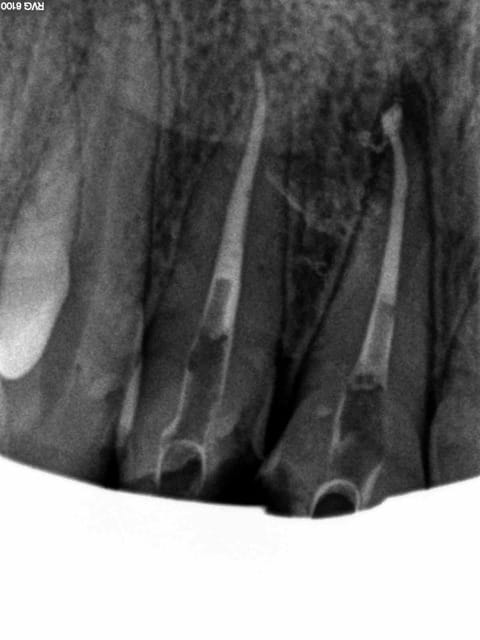

Cas concret ...... en cours pause après 3/4 d'heure. taille à suivre, c'est là ou je chie, ca manque de finesse ! -)))))

Noter le repositionnement des cones , en 2 % c'est impossible.